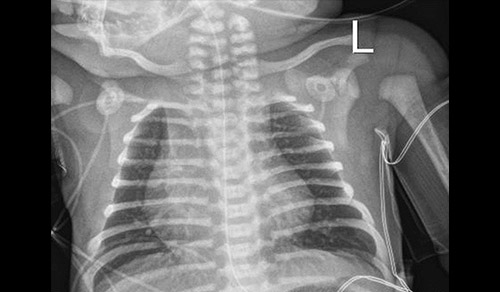

Pediatric pulmonologists from Columbia and Weill Cornell Medicine provide specialized testing and novel therapies for respiratory disorders in children of all ages. Through major centers in cystic fibrosis, asthma, sleep disorders, and aerodigestive and neuromuscular disorders, physicians at the Children's Hospital of New York partner with the patient and their parents to personalize treatment, including participation in clinical trials of the latest therapies, with the goal of helping young patients lead a normal and healthy childhood.

Pediatric Pulmonology